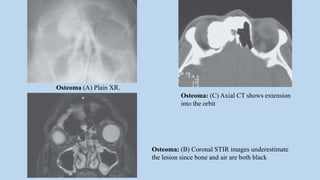

Osteoma: (C) Axial CT shows extension

into the orbit

Osteoma: (B) Coronal STIR images underestimate

the lesion since bone and air are both black

Osteoma (A) Plain XR.